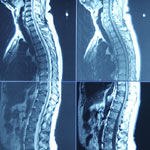

היצרות תעלת השדרה מאובחנת, בדרך כלל, באנשים מבוגרים, כאשר...

תהליכי ניוון בגיל מבוגר גורמים להיצרות תעלת עמוד השדרה,...

שינויים ספונדילוטיים הנם שינויים ניווניים המתפתחים עם הגיל והם ן חלק מן הץמונה ה"נורמלית" בגיל מעל 40 . היצרות תעלת השדרה ( התעלה הספינלית) עלולה לגרום להתפתחות נזק נוירולוגי ( מיאלופתיה צווארית)

היצרות תעלת עמוד שדרה צווארי עלולה להיות תוצאה של תהליכי...